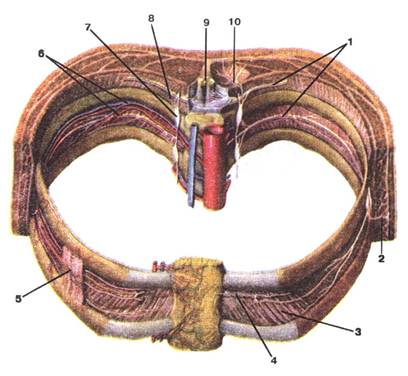

Малюнок А. 10 – Nervi intercortales:

1 -nn. intercostales; 2 -r. cutaneus lateralis; 3 -m. intercostalis internus; 4 -r. cutaneus anterior; 5 -m. intercostalis externus; 6 -arteria et vena intercostales posteriores; 7 -truncus sympathicus; 8 -rr. communicantes trunci sympathici с n. intercostalis; 9 -medulla spinalis; 10 -r. posterior (n. thoracicus)